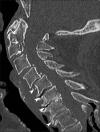

Musculoskeletal disorders are among the most common problems affecting the elderly. The resulting loss of mobility and physical independence can be particularly devastating in this population. The aim of this article is to present some of the most frequent musculoskeletal disorders of the elderly, such as fractures, osteoporosis, osteoarthritis, microcrystal disorders, infections, and tumors.